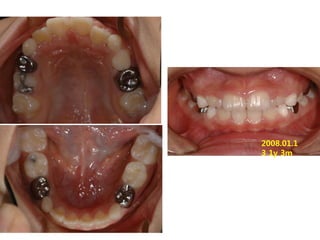

1999.11.24 /F

C.C

• Ant. crossbite, crowding

Dx

• Incorrect tongue posture and mentalis action

Goal

• Establish normal tongue posture and swallowing

pattern

2006.09.07

2006.10.27 Start T4K

2007.02.02 4m

2008.01.1

3 1y 3m

2008.10.04 2y

2009.08.04 2y 10m